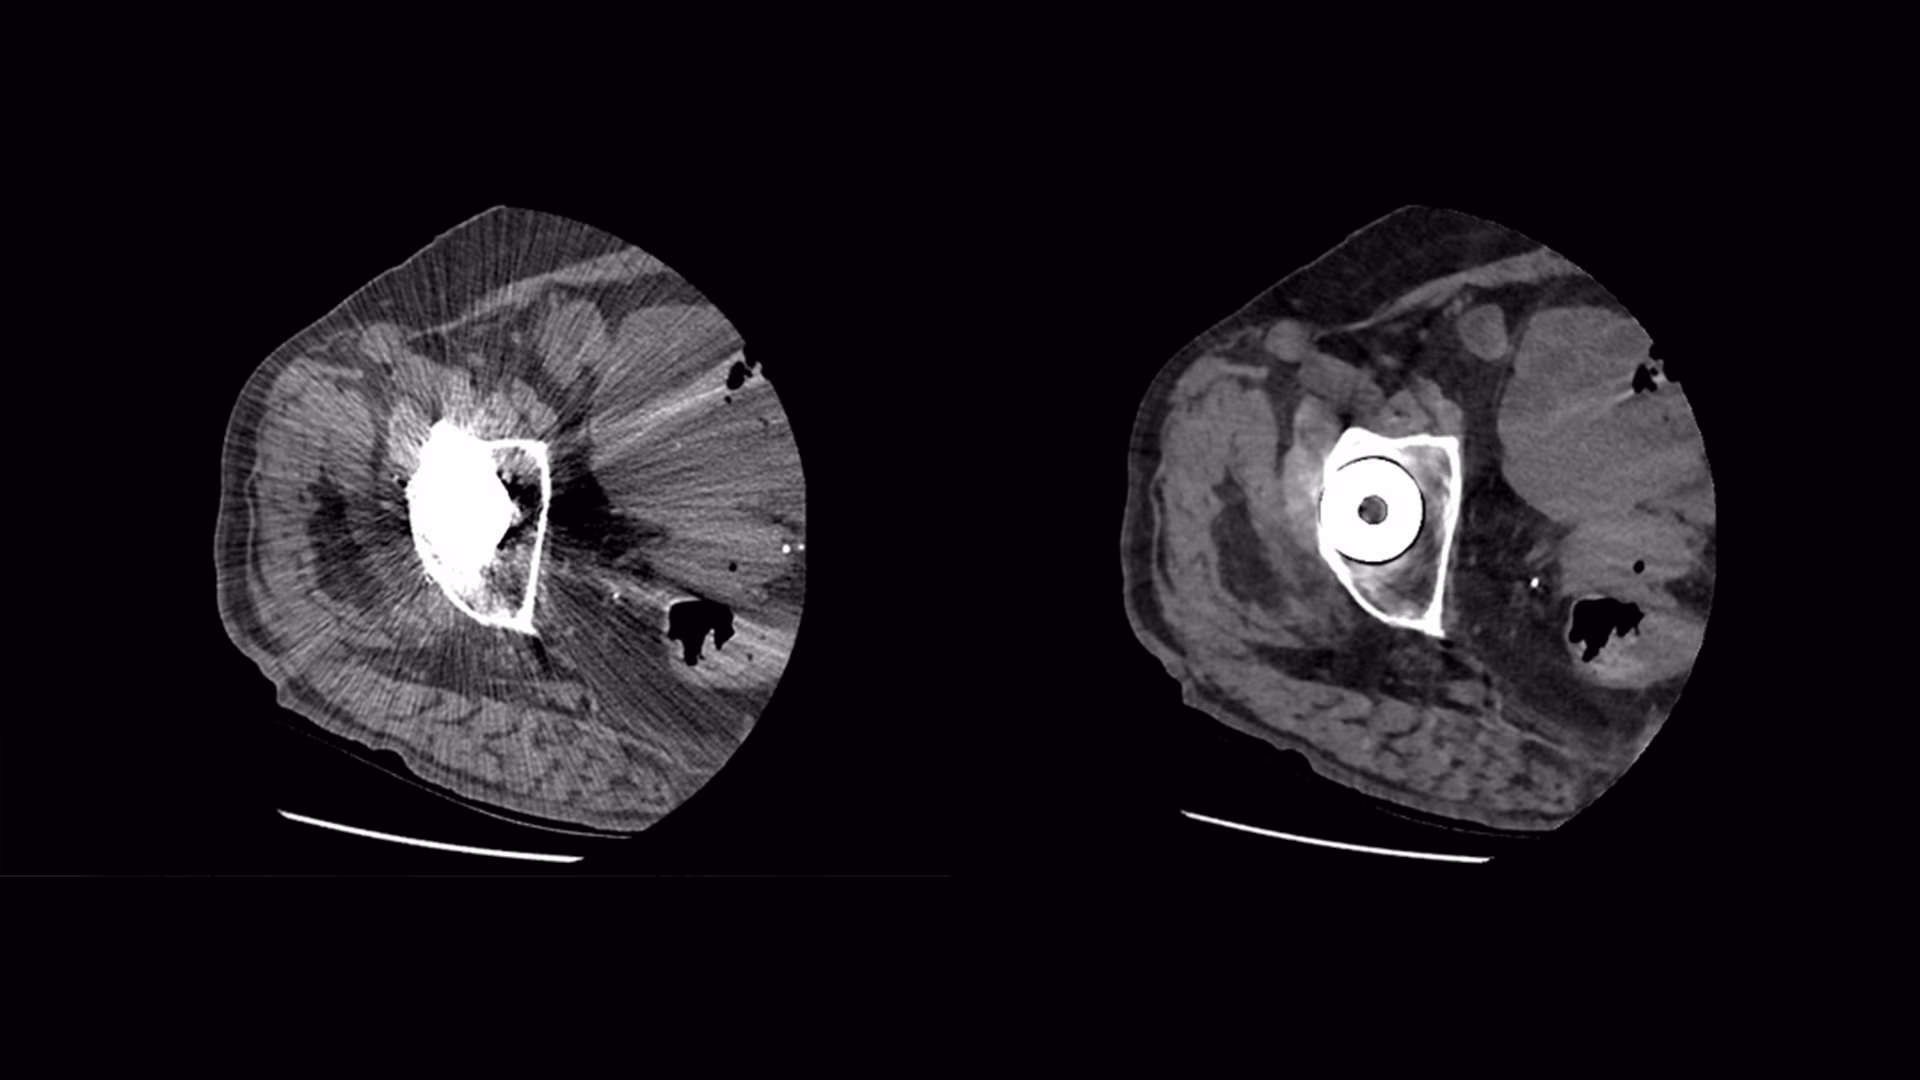

Pelvic CT

Our Revolution Maxima CT is a powerful, reliable system that makes your pelvic scan quick and comfortable. With cutting-edge technology, it provides clear, detailed images to identify issues such as pelvic pain, abnormal growths, or other concerns, ensuring you get answers you can trust.

We prioritize your comfort every step of the way. A Pelvic CT is a non-invasive procedure that takes detailed pictures of your pelvic area. You’ll lie on a comfortable table as the Revolution Maxima CT scanner captures images in just a few minutes. Our friendly team will guide you through the process, answer any questions, and ensure you feel at ease.